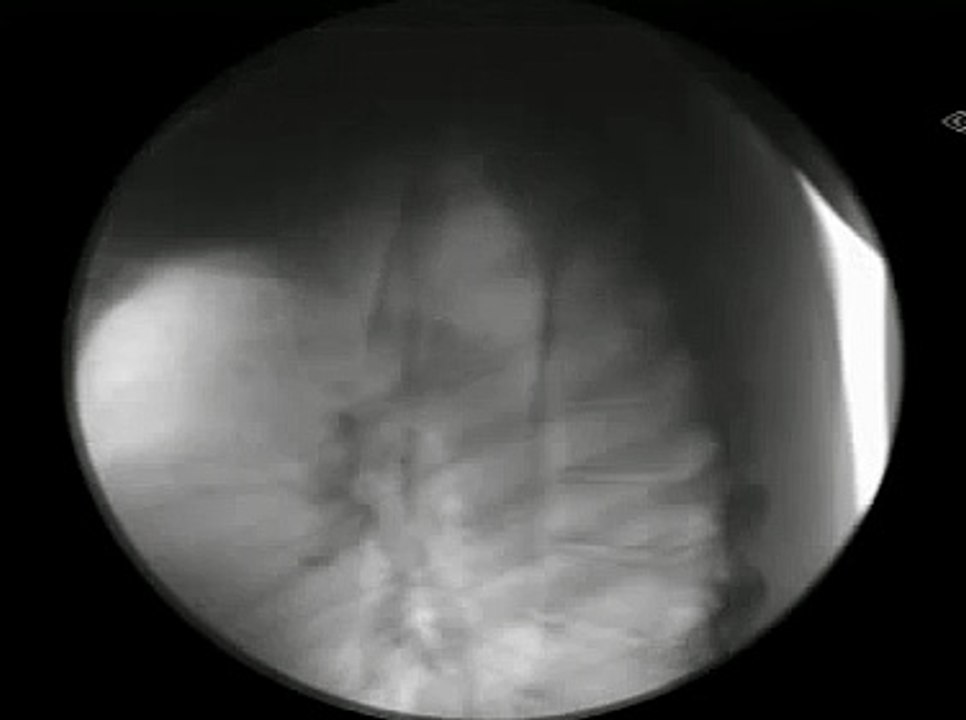

A dangerous magical act where Dr. Gertes swallowed a solid stainless metallic sword ! ! !